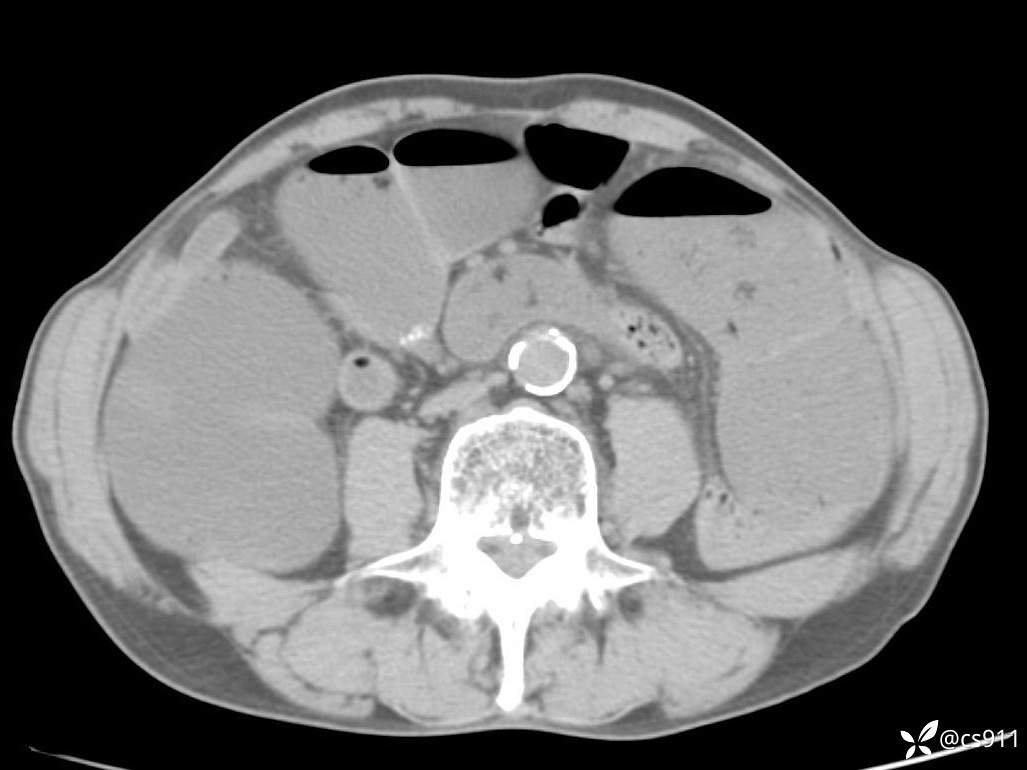

急腹症之急诊CT,原因?答案公布

男,77岁,腹痛、腹胀伴恶心呕吐1天。呕吐胃内容物,非喷射性呕吐,有咖啡色样胃内容物,诉有胃穿孔病史。查体:全腹平,下腹部压痛,全腹无反跳痛,叩诊呈浊音,移动性浊音阴性,肠鸣音减弱,1-2次/分。肛检:直肠未扪及明显肿物,可触及大量粪块。

血淀粉酶(AMY) HH 1859 U/L 35-135